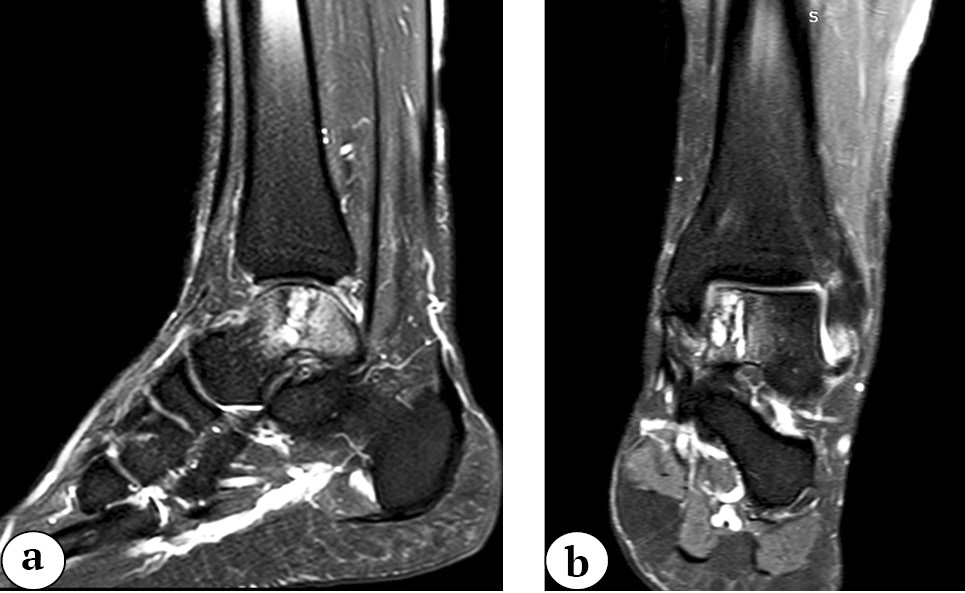

Было выполнено МРТ левого голеностопного сустава: прослеживался гетерогенный сигнал в медиальном отделе купола таранной кости, выявлены хондромаляция суставной поверхности, перестройка костной ткани медиального отдела таранной кости. В области медиального купола таранной кости определялся остеохондральный дефект размерами 16,4×9,4×20,8 мм (рис. 1).

Рис. 1. МРТ левого голеностопного сустава, мультипланарная реконструкция (Т2-взвешенное изображение): a — фронтальная плоскость; b — сагиттальная плоскость

Fig. 1. MRI of the left ankle, multiplanar reconstruction (T2-weighted image): a — frontal plane; b — sagittal plane